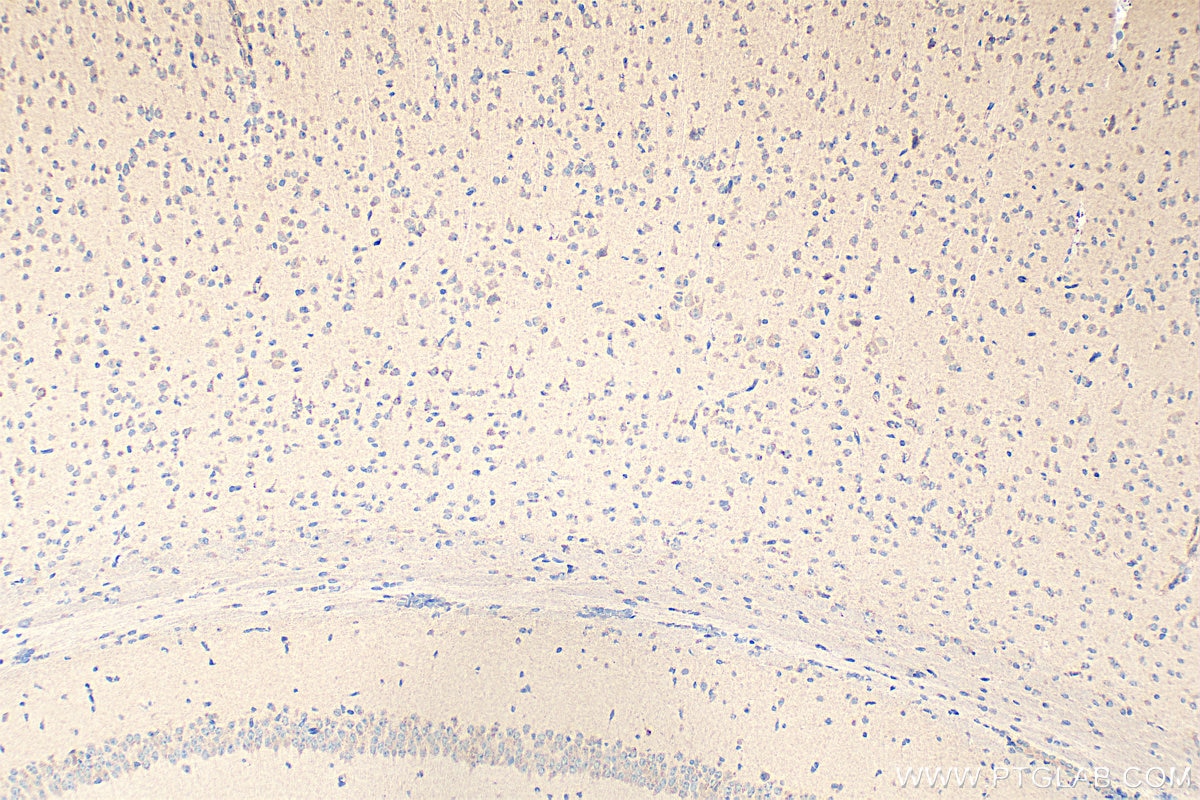

| Positive IHC detected in | human pancreas tissue, human stomach tissue, mouse brain tissue Note: suggested antigen retrieval with TE buffer pH 9.0; (*) Alternatively, antigen retrieval may be performed with citrate buffer pH 6.0 |

13074-2-AP targets CCK in IHC, IF, ELISA, Cell treatment applications and shows reactivity with human, mouse samples.